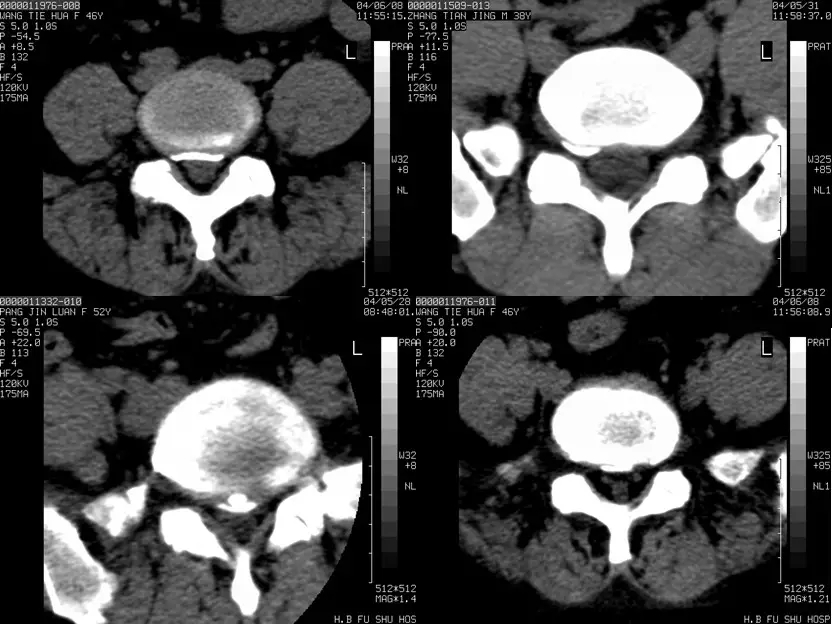

椎间盘突出的CT表现

直接征象:A、椎间盘后缘向椎管内局限性突出,密度与相应椎间盘一致,形态不一。B、突出的椎间盘可有大小、形态不一的钙化,多与椎间盘相连;C、椎管内硬膜外可见髓核游离碎片,密度高于硬膜囊;D、许莫结节表现为椎体上(下)缘边缘清楚的隐窝状压迹,多位于椎体中后1/3交界部,常上下对称出现。其中心密度低,为突出的髓核及软骨板,外周为反应性骨硬化带。

间接征象:A、硬膜外脂肪间隙变窄、移位、或消失。B、硬膜囊前缘或侧方及神经根受压移位。C、周围骨结构改变,突出髓核周围骨质硬化。

椎间盘突出图像

椎间盘突出(中央型)

中央型

椎间盘突出右旁中央型

椎间盘突出左旁中央型

椎间盘膨出

椎间盘膨出伴右后突出